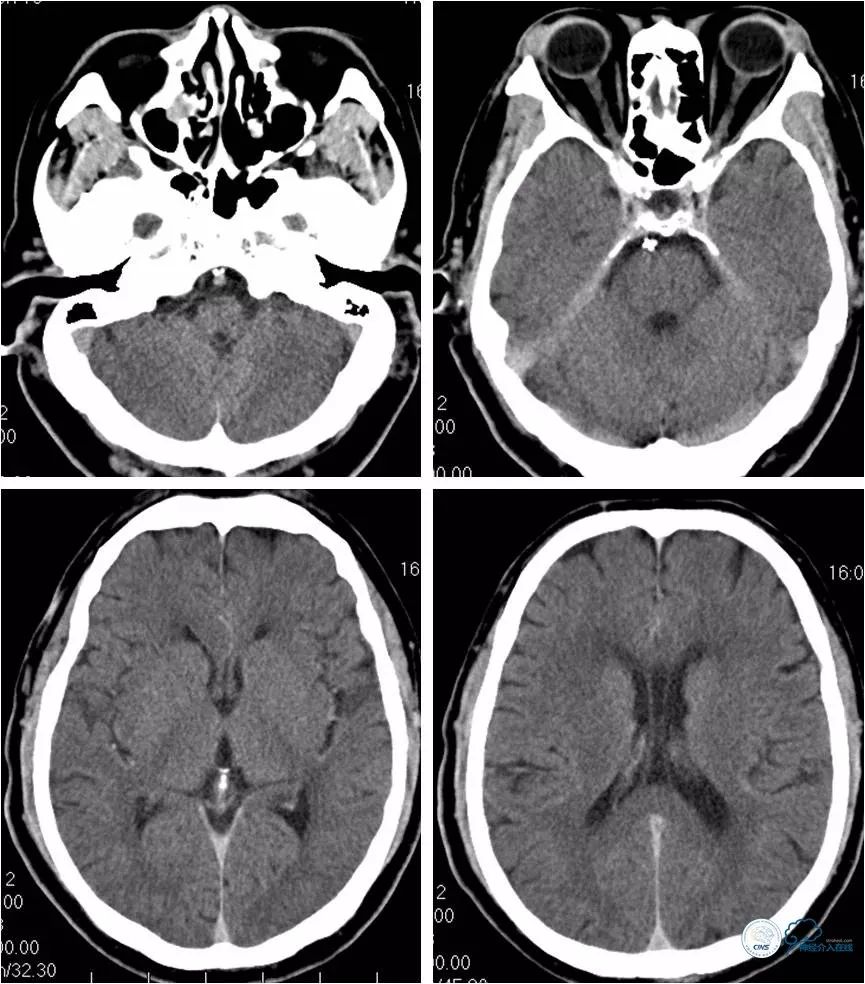

入院后头颅MR(2018-6-30):DWI未见明显新鲜梗死病灶(图1)。

图1

术后立即复查头CT未见出血(图15)。

图15